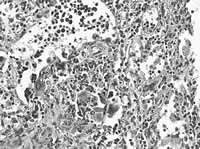

肺功能检测:限制性通气功能障碍,弥散功能障碍。肝脾病理:肝脾原因不明髓外造血伴吞噬红细胞现象(见图);脾多发坏死;肝片状出血;淋巴结反应性增生。免疫组化:

CD15(++)、MAC(++)、CD3(+)、CD43(++)、NK1(+)、CD20(-)、CD79 α(-)。

图 遥髓外造血,胖吞噬红细胞现象

宋合斌(病理科医师):该病人送检为完整切除脾,重1645g,弥漫散在分布灰白和灰黄样粟粒状结节,直径0.05~0.3 cm;送检部分肝,切面可见灰黄粟粒状结节,直径 0.1~0.2 cm。病理诊断:肝脾原因不明性髓外造血,伴吞噬红细胞现象;脾多发性坏死为碎片样坏死,而非干酪样坏死,坏死周围组织小灶性散在的异型细胞,为巨核细胞,并可见红系粒系造血细胞。特殊染色网织(-)、抗酸(-)、 PAS染色 (-)。免疫组化:CD15(++)、MAC(++)、CD3(+)、CD43(++)、NK1(+)、CD20(-)、CD79 α(-)。